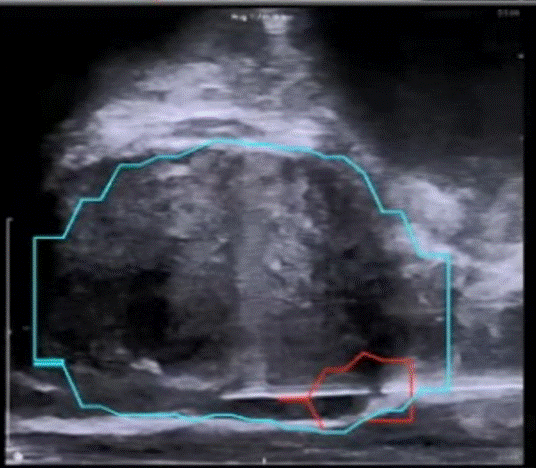

前列腺穿刺的技术不断地在进步,从早期的手指下引导穿刺,到超声下引导穿刺,再到MRI-超声“意念融合”穿刺。幸运地是,现在已经实现MRI与超声融合引导下穿刺。该技术将患者的MRI图片导入电脑软件,然后与患者的前列腺超声图像融合,这样可以在超声图像上显示出MRI提示的病灶,实现更加精确的穿刺,提高了确诊率,减少漏诊。从下面的超声图中可以看到,通过磁共振的信息,勾勒出蓝色的前列腺轮廓,红色的前列腺癌可疑病灶,这是以前单纯超声无法实现的。

磁共振/超声融合靶向穿刺技术示意图。图片来源:BK ultrasound